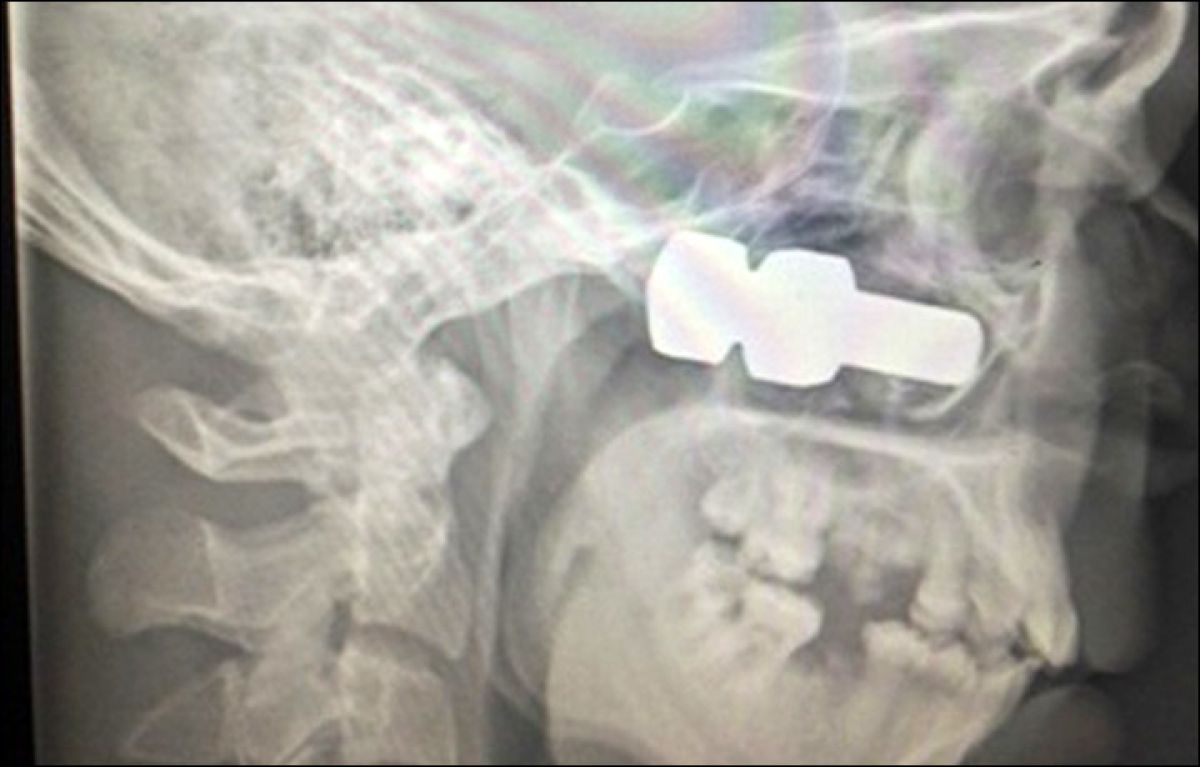

Tujek v glavi je razkril šele rentgen.

Na pomoč mu je priskočil voznik nekega drugega vozila, ki je opazil, da je prišlo do nesreče, in ustavil. Skupaj sta počakala na rešilca, v bolnišnici pa so mu rano na obrazu skrbno zašili, a s tem se njegove zdravstvene tegobe niso končale. Rentgenski pregled je pozneje namreč pokazal, da ima v desnem sinusu v bližini očesa zagozden 6,2 centimetra dolg vijak z matico. Nemudoma so ga prepeljali v regionalno bolnišnico in ga naslednje jutro operirali. Po navedbah kirurga Ivana Kana so ga od izgube očesa ali celo življenja ločili centimetri. Anton z desnim očesom zaenkrat še ne vidi, a se odziva na svetlobo. Zdravniki upajo, da se mu bo vid povrnil, ko se mu bo zmanjšala oteklina.

Vijak je dolg dobrih šest centimetrov.

Lahko bi izgubil oko ali celo življenje.